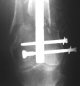

Attached are few examples from our Hospital:

A. Difficult reductions, even in retrograde nailing (my preference, easier control of "small" distal fragment) and it is much, much harder to do it anterograde (Alex, do you have one good case in your collection of anterograde nailing in very distal fractures - as you have suggested that I

should have done it in my previously posted case?

Malpositioning is much too common (recurvatum, varus - valgus).

B. Fixation loosening: distal cutting of the nail, non-unions do happen (cases attached).

Locking Plating has more distal screws than any nail, fixed angles and provides much better fixation, especially in osteoporotic bone.